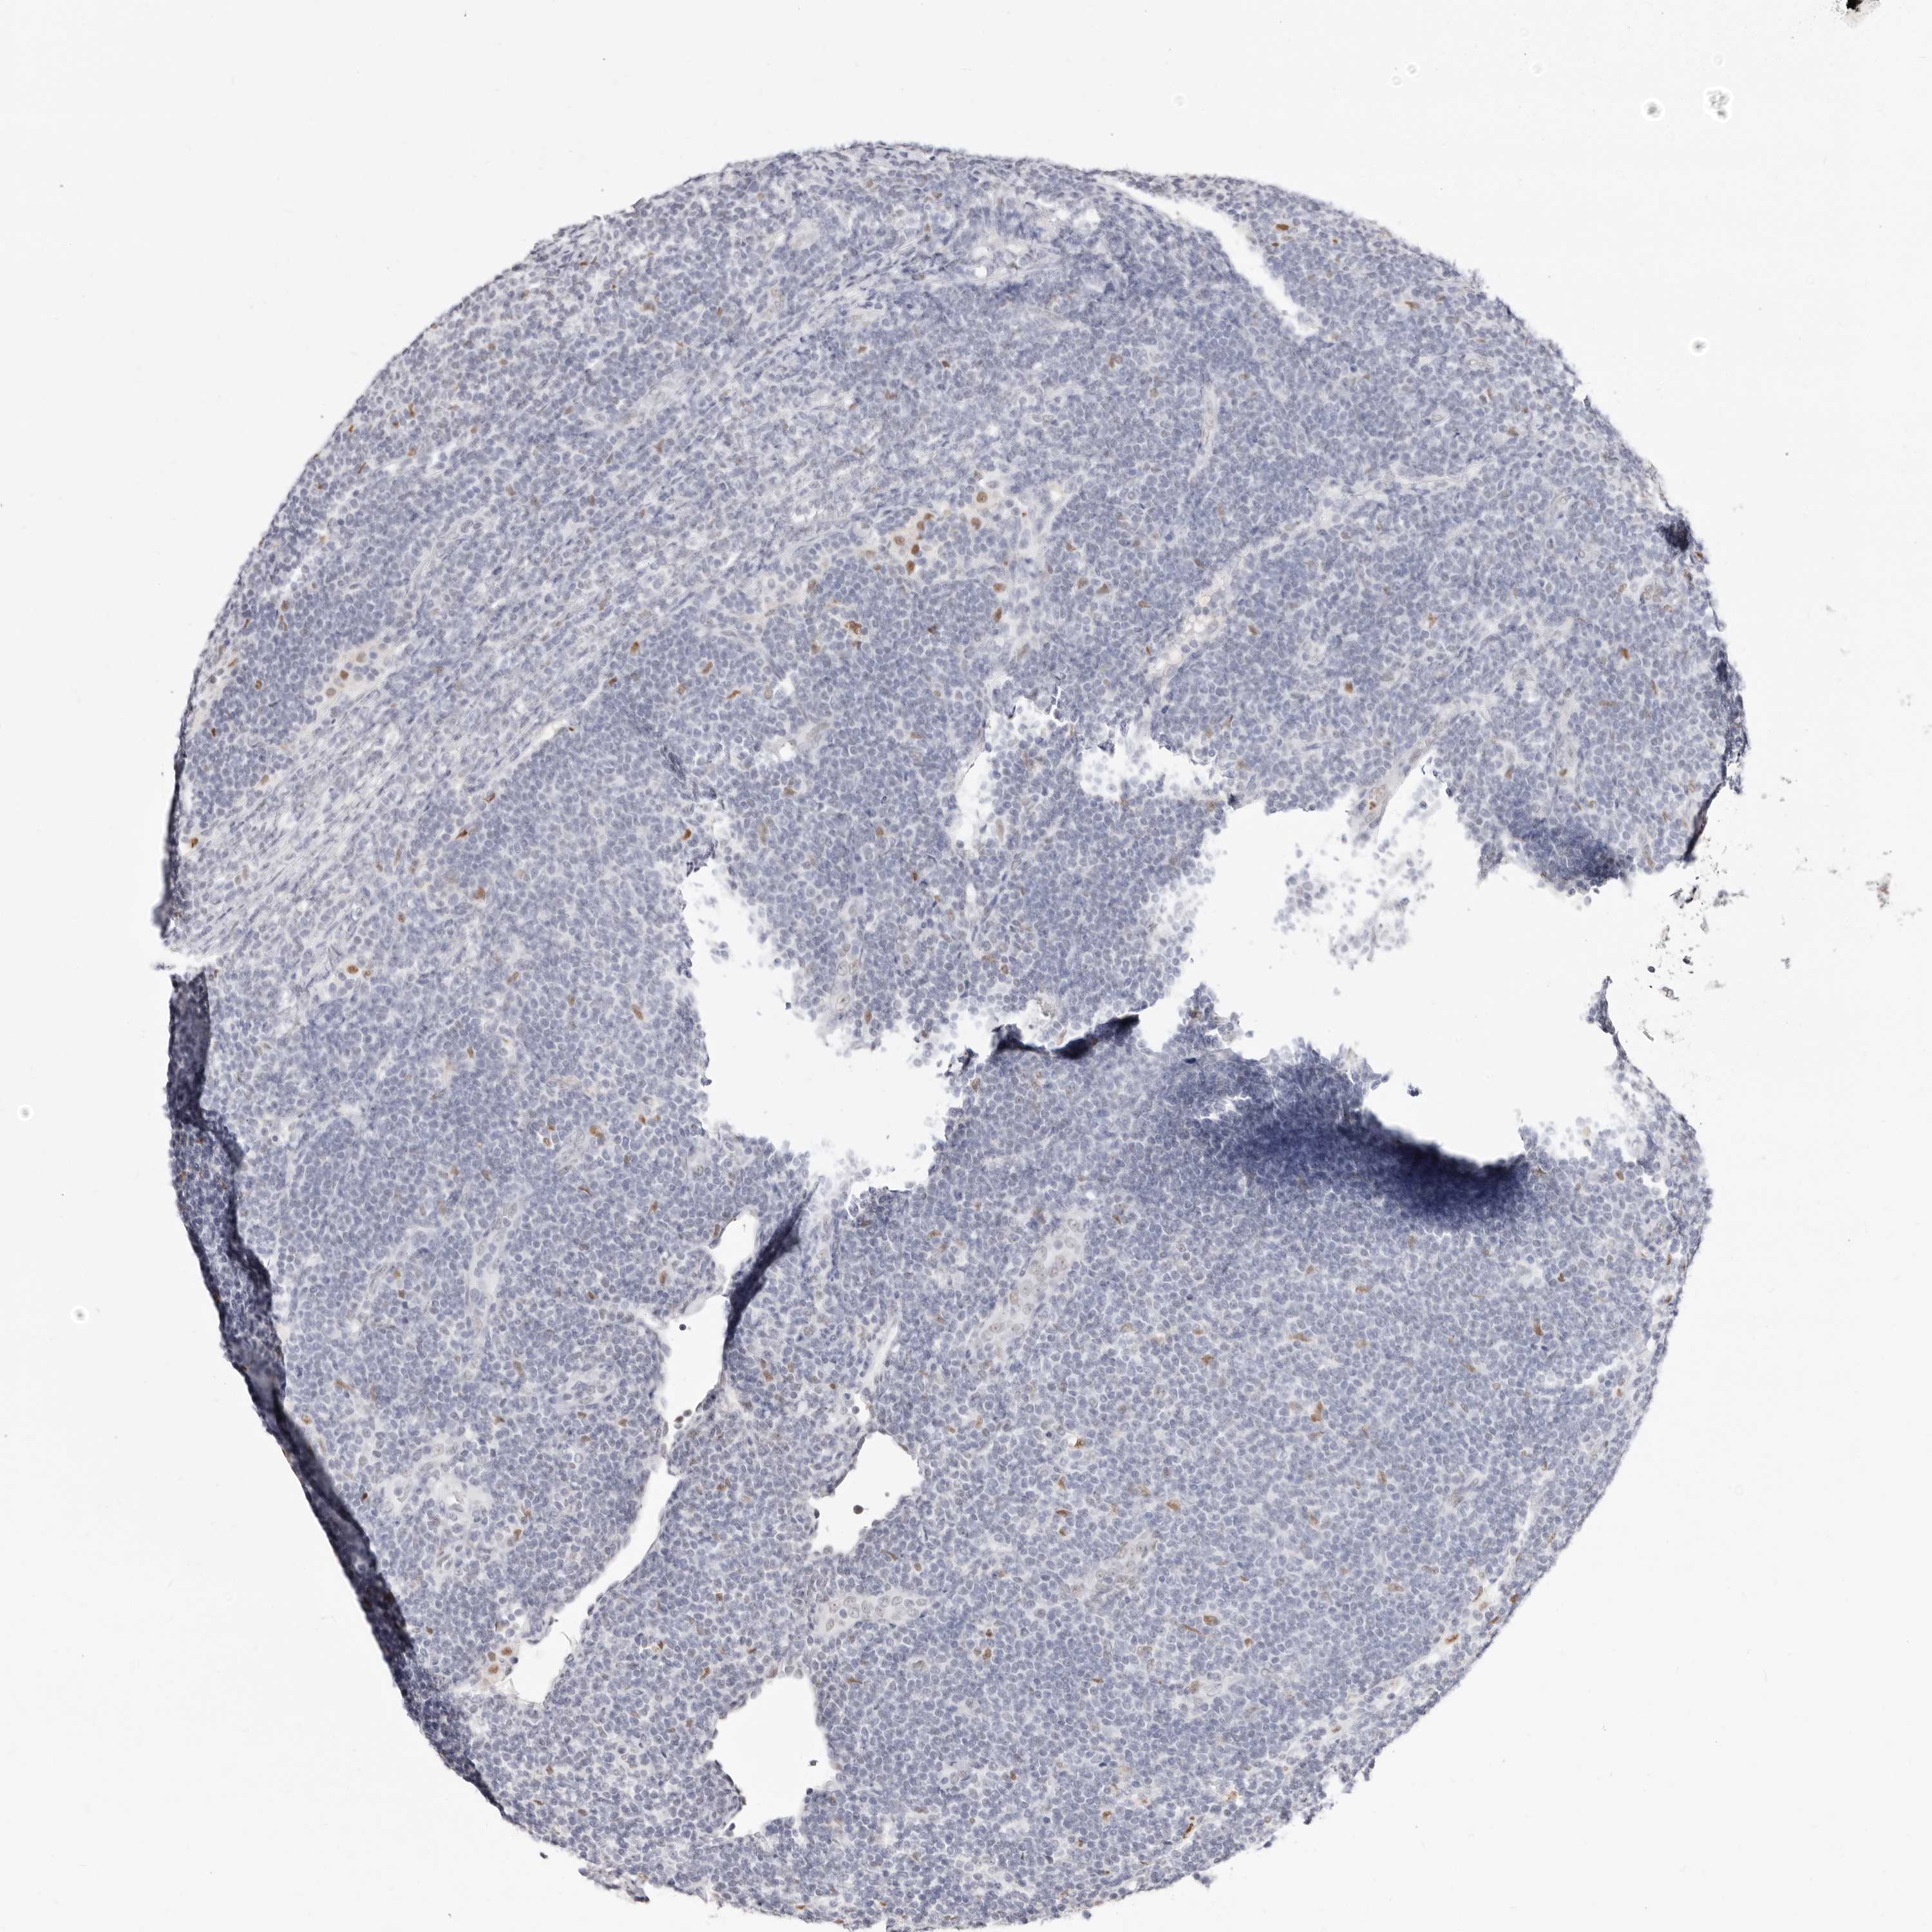

LYMPHOMA - Protein expressioni

A mouse-over function shows sample information and annotation data. Click on an image to view it in a full screen mode. Samples can be filtered based on level of antibody staining by selecting one or several of the following categories: high, medium, low and not detected. The assay and annotation is described here.

Antibody stainingi

Antibody staining in the annotated cell types in the current human tissue is reported as not detected, low, medium, or high, based on conventional immunohistochemistry profiling in selected tissues. This score is based on the combination of the staining intensity and fraction of stained cells.

Each image is clickable and will lead to virtual microscopy that enables deeper exploration of all samples and also displays staining intensity scores, fraction scores and subcellular localization as well as patient and tissue information for each sample.

Antibody HPA029481

Intensity

Strong

Moderate

Weak

Negative

Quantity

>75%

75%-25%

<25%

None

Location

Nuclear

Cytoplasmic/membranous

Cytoplasmic/membranous,nuclear